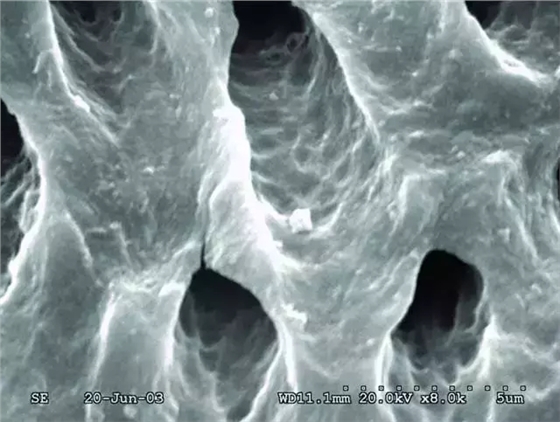

次氯酸鈉和EDTA沖洗預(yù)備后的根管壁。玷污層已去除,牙本質(zhì)小管打開了,并且很潔凈。

高倍鏡下上圖中的牙本質(zhì)表面